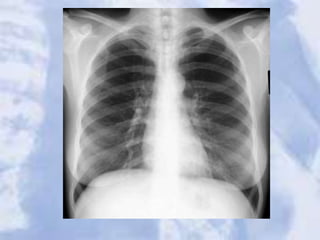

The Normal Chest X-ray

• PA View:

1. Aortic arch

2. Pulmonary trunk

3. Left atrial appendage

4. Left ventricle

5. Right ventricle

6. Superior vena cava

7. Right hemidiaphragm

8. Left hemidiaphragm

9. Horizontal fissure